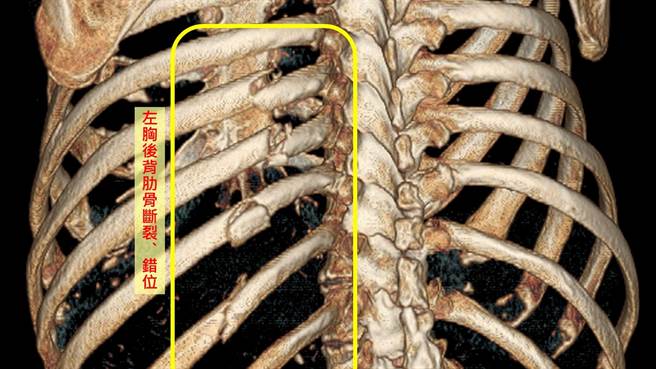

电脑断层扫瞄影像显示廖姓老翁肋骨断裂、错位。(台中慈济医院提供/王文吉台中传真)

台中94岁廖姓老翁日前在浴室滑倒,紧急送台中慈济医院急诊。胸腔外科主任吴政元会诊发现,老翁左侧背后肋骨有四处断裂,若採用保守疗法,病人会因持续疼痛,生活品质低落。家属讨论后决定施行肋骨骨板手术固定,顺利解除老翁疼痛,住院一周后出院,恢復正常生活。

廖翁状况特别严重,肋骨已经断裂、错位及碎片存留,且位置在背部,即使住院躺床都很不舒服,止痛药亦无法改善。麻醉科评估认为老先生身体状况可接受麻醉与手术,家属讨论后採用肋骨专用钛合金骨板固定手术,固定肋骨骨折部位。